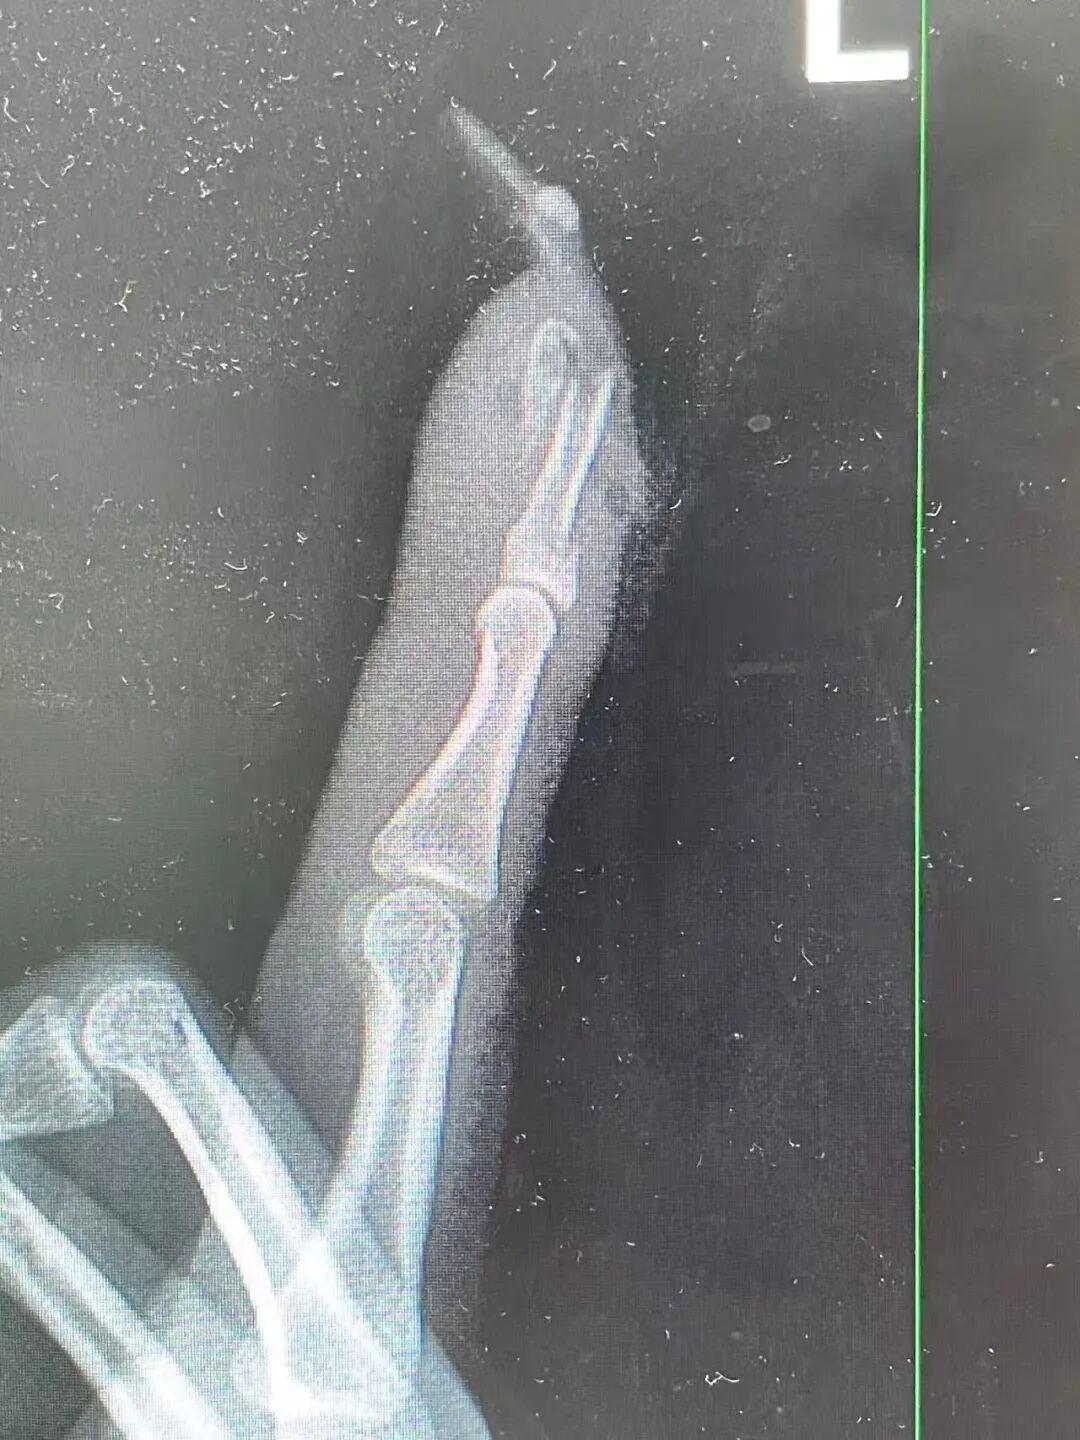

“食指指骨骨折,甲床翻脸。”接诊的骨科医师曹立查验后发现王女士指甲断裂,部分甲床外露,需要手术竖立。曹医师坐窝为王女士进行指骨骨折闭合复位内固定术,术后规复浩繁。曹医师暗示,若是莫得好意思甲,伤害不会这样严重。